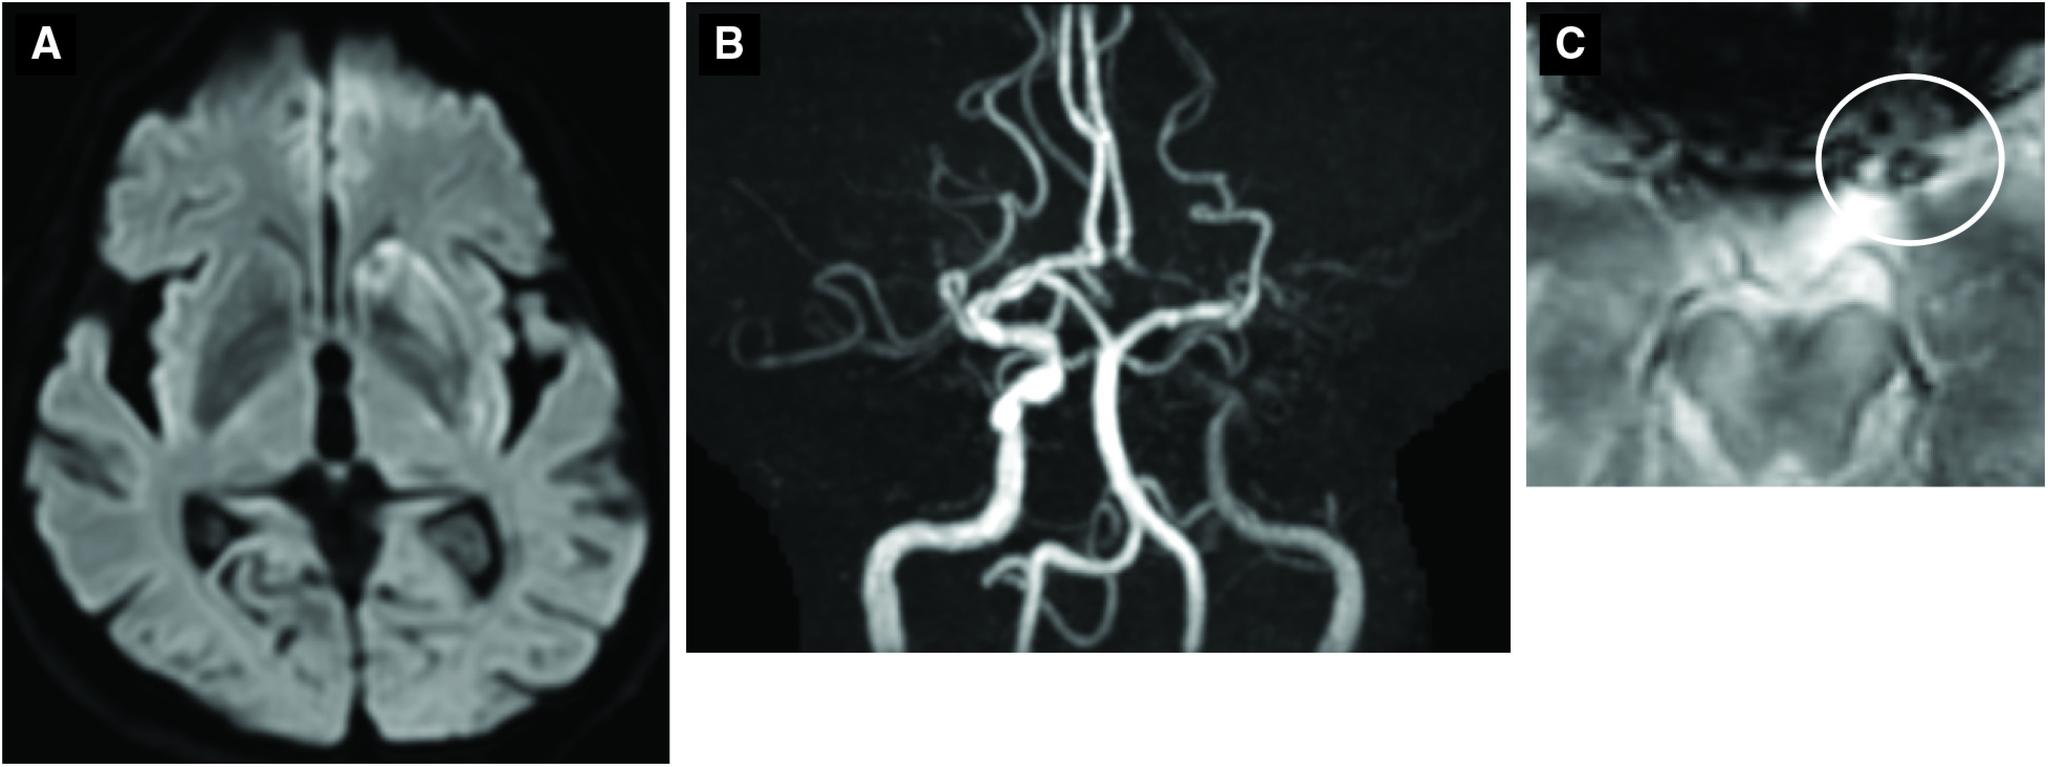

CASE PRESENTATION

A 73-year-old woman was diagnosed with moyamoya disease by asymptomatic right middle cerebral artery occlusion at 59 years of age. The patient was transported for stroke symptoms. Magnetic resonance imaging (MRI) demonstrated left terminal internal carotid artery occlusion and low-intensity signal on T2*-weighted imaging at the occlusion site. Alteplase was administered and endovascular treatment was subsequently performed. A small-diameter microcatheter was guided to the distal end of the occlusion and angiography after deployment of a stent retriever revealed irregular stenosis. Severe stenosis remained after thrombectomy, and balloon angioplasty was added. The treatment resulted in recanalization and good outcome.

一名73岁女性在59岁时因无症状性右侧大脑中动脉闭塞被诊断为烟雾病。该患者因中风症状被送来就诊。磁共振成像(MRI)显示左颈内动脉末端闭塞,闭塞部位在T2*加权成像上呈低强度信号。给予了阿替普酶并随后进行了血管内治疗。将一根小直径微导管引导至闭塞远端,在部署支架取栓器后进行血管造影显示不规则狭窄。取栓术后仍存在严重狭窄,遂加用球囊血管成形术。治疗导致血管再通且预后良好。